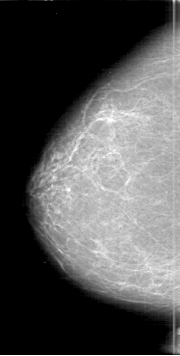

D_4189_1.LEFT_MLO

RIGHT_CC LINES 6391 PIXELS_PER_LINE 3226 BITS_PER_PIXEL 12 RESOLUTION 43.5 NON_OVERLAY